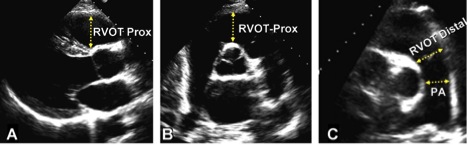

Зріз PSAX на рівні клапану легеневої артерії (КЛА) демонструє «дистальний діаметр» ВТПШ (Рис. 8C), у той час як доступ PLAX дозволяє вимір проксимальної частини ВТПШ, що також називають його «проксимальним діаметром» (Рис. 8A). Діаметр >27 мм в кінці діастоли на рівні прикріплення КЛА («дистальний діаметр») вказує на дилатацію ВТПШ.

Рис. 8. Виміри розмірів виносного тракту ПШ (RVOT) на проксимальному або подклапанному рівні (RVOT-Prox) та на дистальному рівні, або дистальному рівні (RVOT-Distal) в (A) парастеранальній позиції по довгій вісі ЛШ (візуалізується передня частина ВТПШ, (B) парастернальній позиції по короткій вісі на рівні магістральних судин, та (C) парастернальній позиції по короткій вісі на рівні біфуркації ЛА. PA – поперечний розмір ЛА на рівні між КЛА та її біфуркацією.